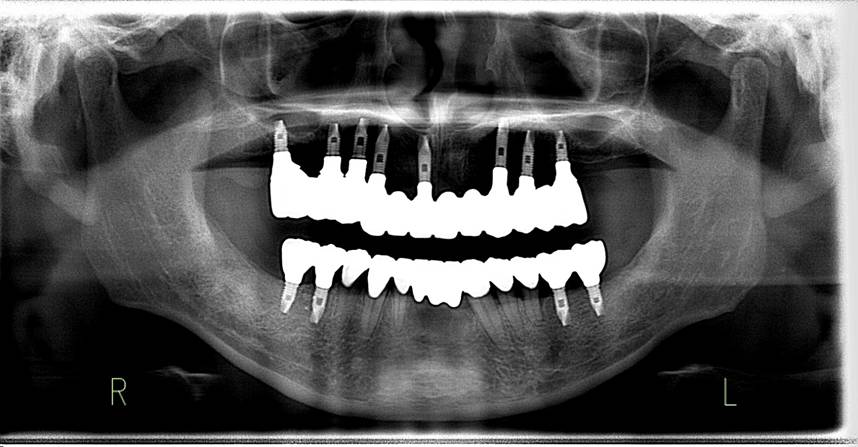

術前パノラマレントゲン写真。根の周りが黒くなり、骨がなくなっていることがわかります

治療後。歯周病で失われた骨が回復しています。使用インプラントはスプラインツイストです。